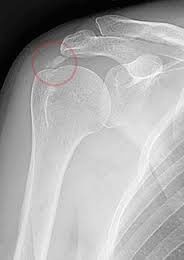

Εικόνα με ακτινογραφία ώμου στην οποία εμφανίζεται η ασβεστοποίηση.

Η διάγνωση, γίνεται κλινικά και επιβεβαιώνεται με ακτινολογικό έλεγχο, ενώ σημαντικές πληροφορίες προσφέρουν τόσο το υπερηχογράφημα, όσο

και η μαγνητική τομογραφία (MRI) για ανακάλυψη συνοδών βλαβών του ώμου όπως εκφυλίσεις και ρήξεις τενόντων.